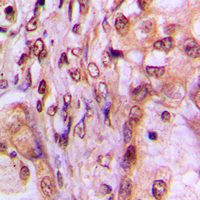

IHC (Immunohiostchemistry)

(Immunohistochemical analysis of MAF1 staining in human breast cancer formalin fixed paraffin embedded tissue section. The section was pre-treated using heat mediated antigen retrieval with sodium citrate buffer (pH 6.0). The section was then incubated with the antibody at room temperature and detected using an HRP conjugated compact polymer system. DAB was used as the chromogen. The section was then counterstained with haematoxylin and mounted with DPX.)